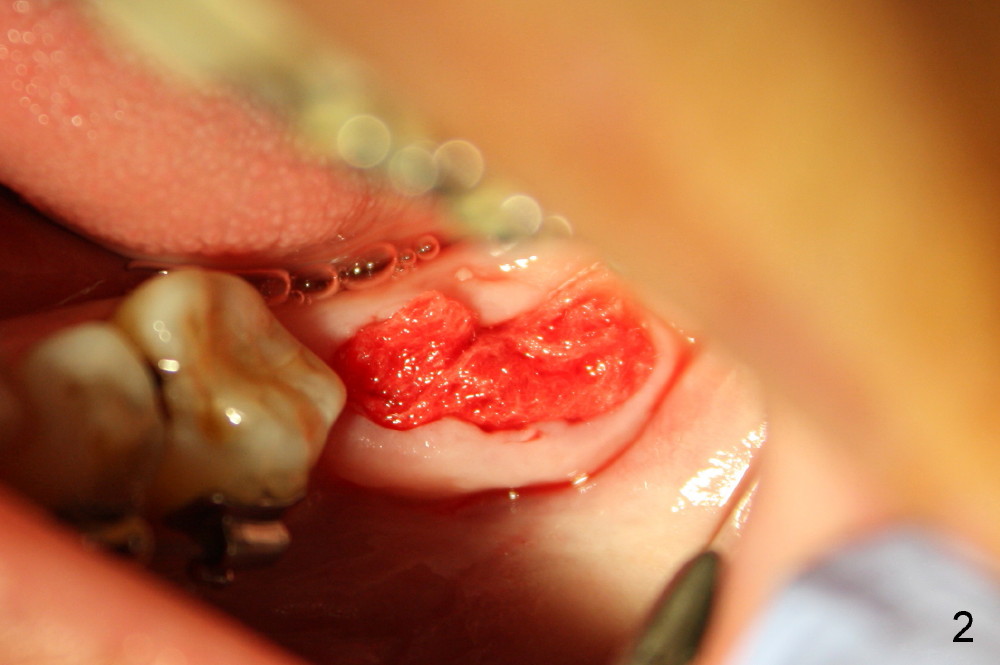

Planning gives the surgery and assistants confidence. Implant placement seems to be more smoothly. A preop PA (Fig.1) shows that the periapical radiolucency of the neighboring tooth #19 disappears. Removal of the residual roots of the teeth #17 and 18 (Fig.1 *) gives rise to a nice surgical field (Fig.2, the sockets packed with Clindamycin soaked gauze). Immediate implant osteotomy is formed as mesial as possible of the wound. Attention is being paid to buccolingual trajectory when the first pilot drill is used (not shown). An intraop PA is taken with a 3.8 mm tap in place to confirm the depth of the osteotomy relative to the inferior alveolar canal (Fig.3). A 4.5x12 mm implant is placed as planned (Fig.4). The elongated wound (mesiodistally) allows the wound to approximate around the implant/healing abutment with sutures (Fig.5). The gingiva heals 8 days postop (Fig.6). The 1st 4 coronal threads remains outside the bone 3.5 months postop (Fig.7 >). It appears that less thread exposure 1 year 7 months postop (Fig.8), suggesting bone growth. To prevent periimplantitis and facilitate restoration, place 2nd molar implant as deep as possible with slightly shorter implant.